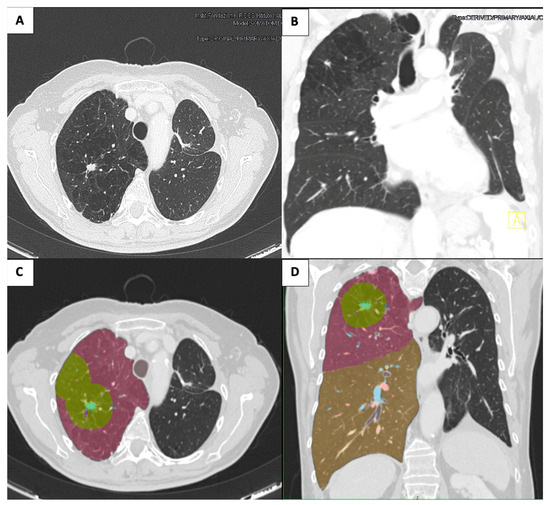

2.3. Case 3